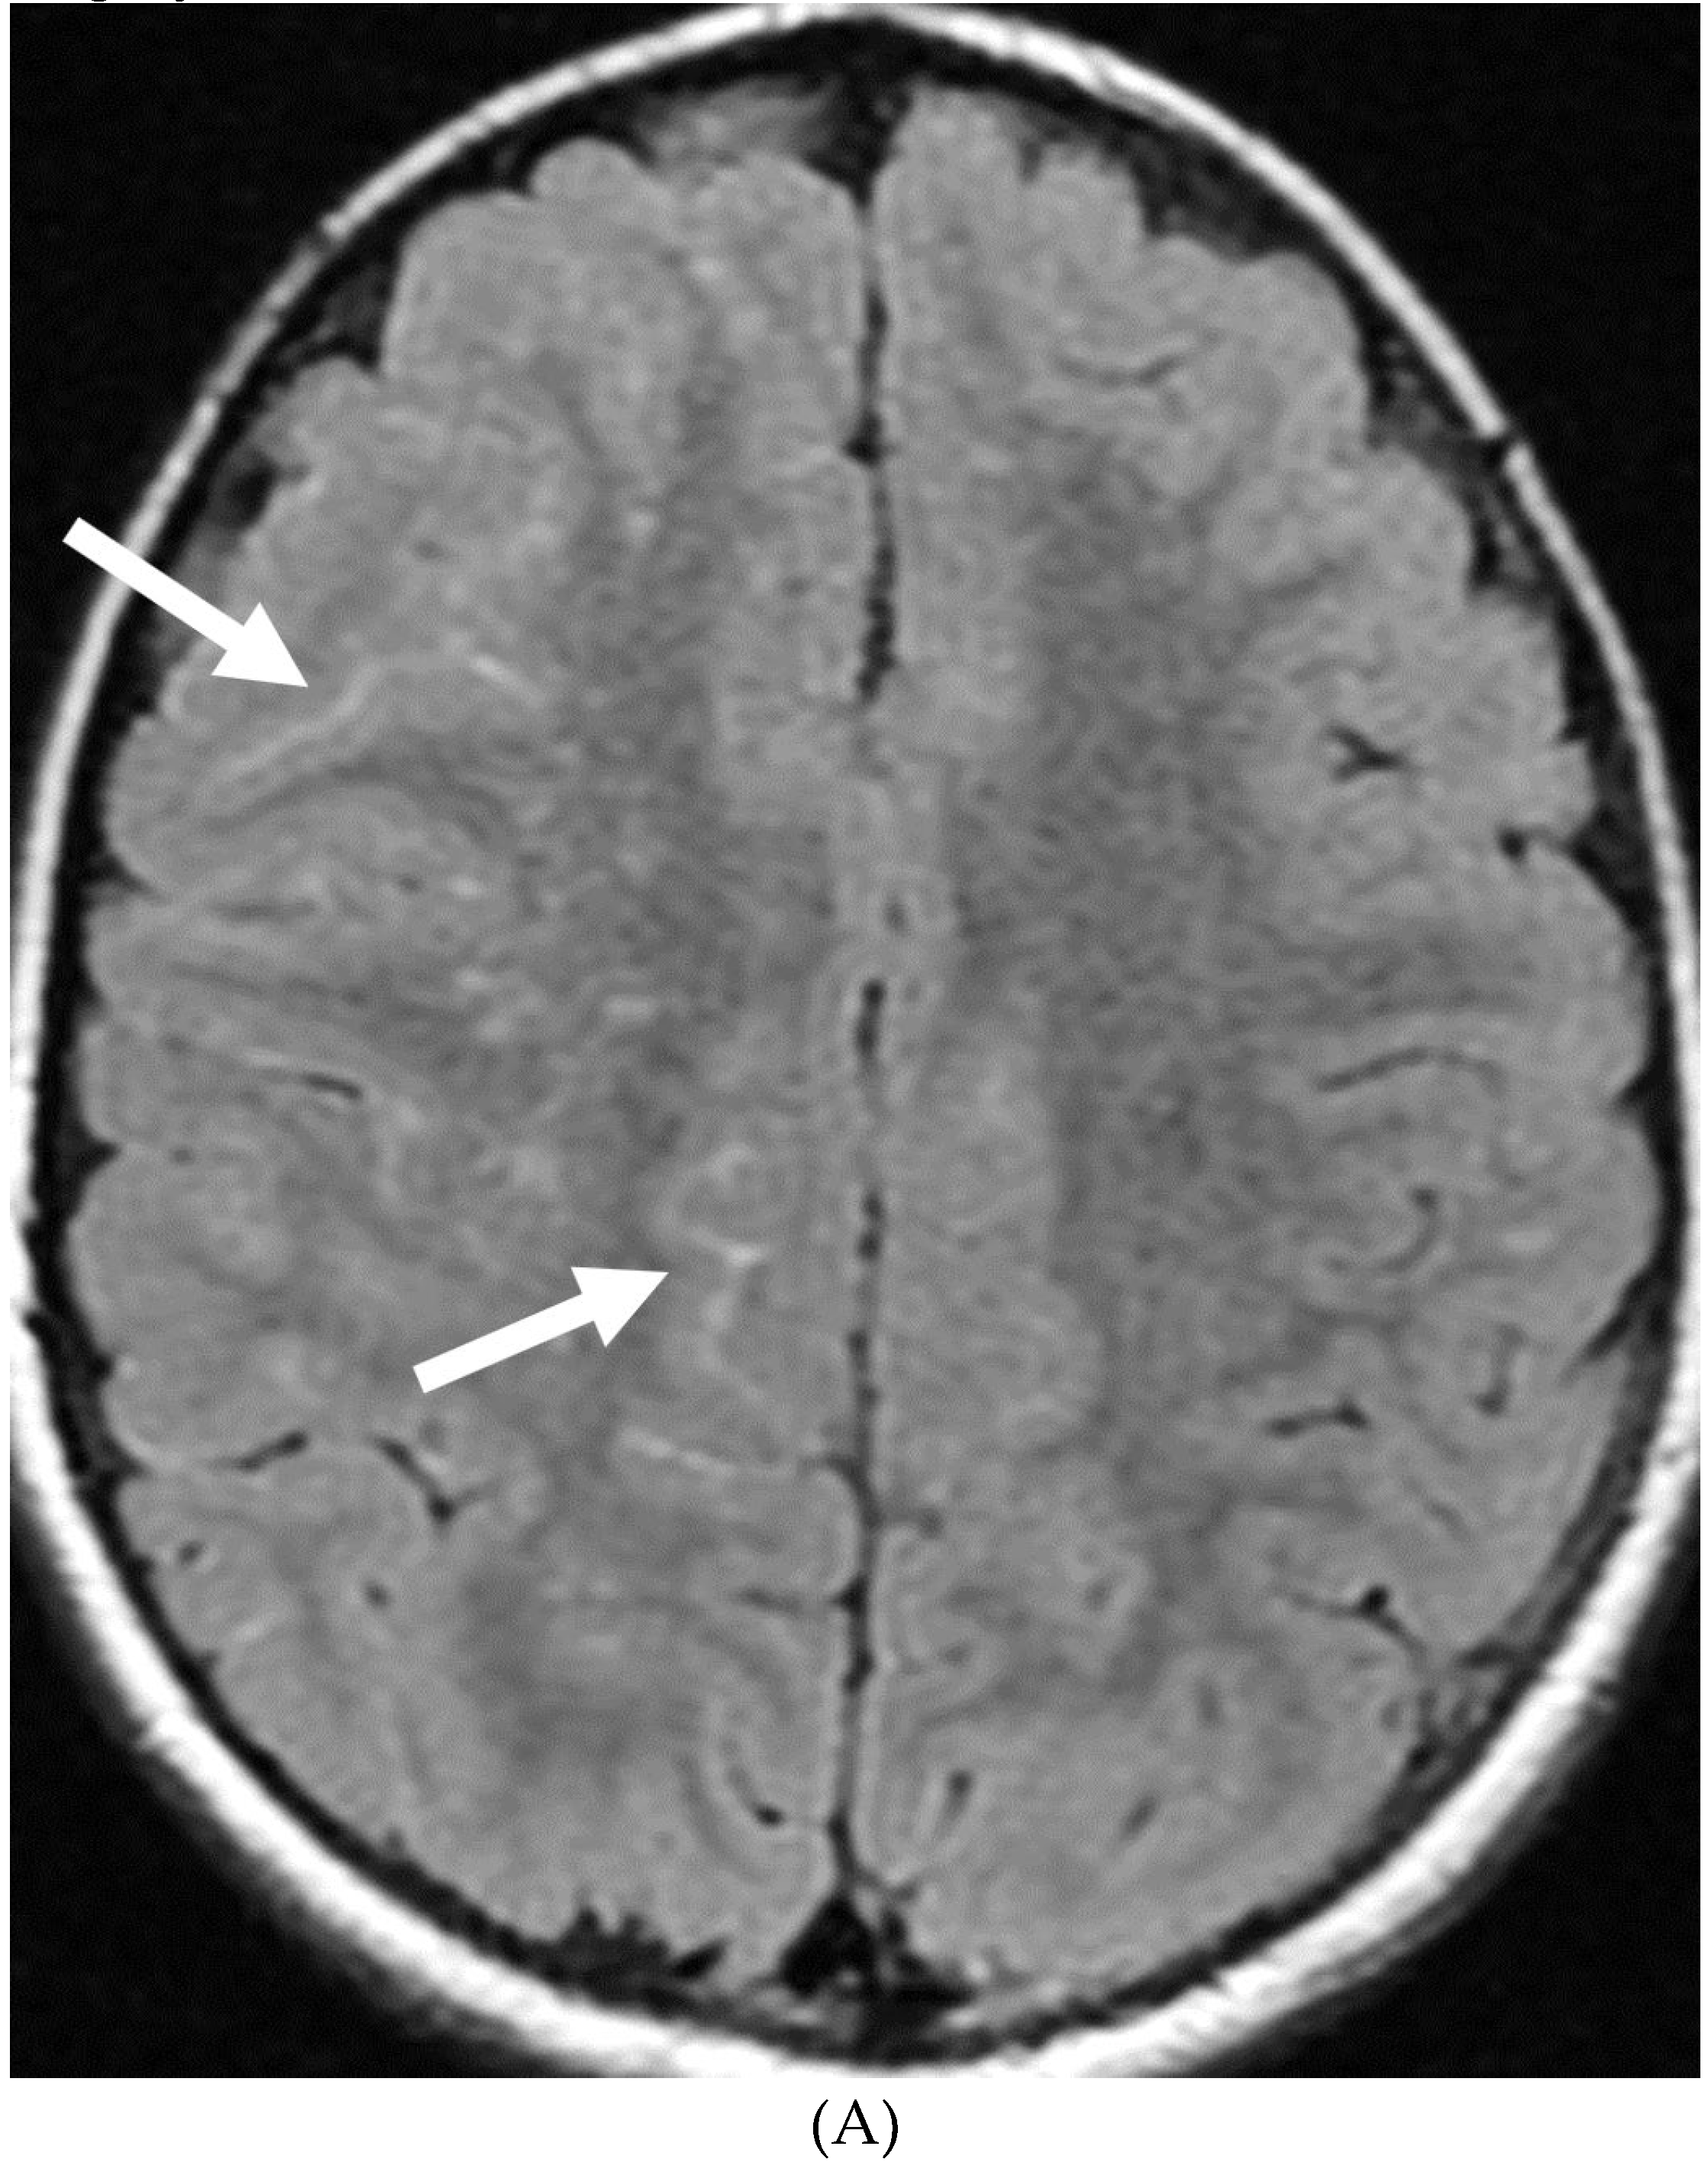

MOYA MOYA